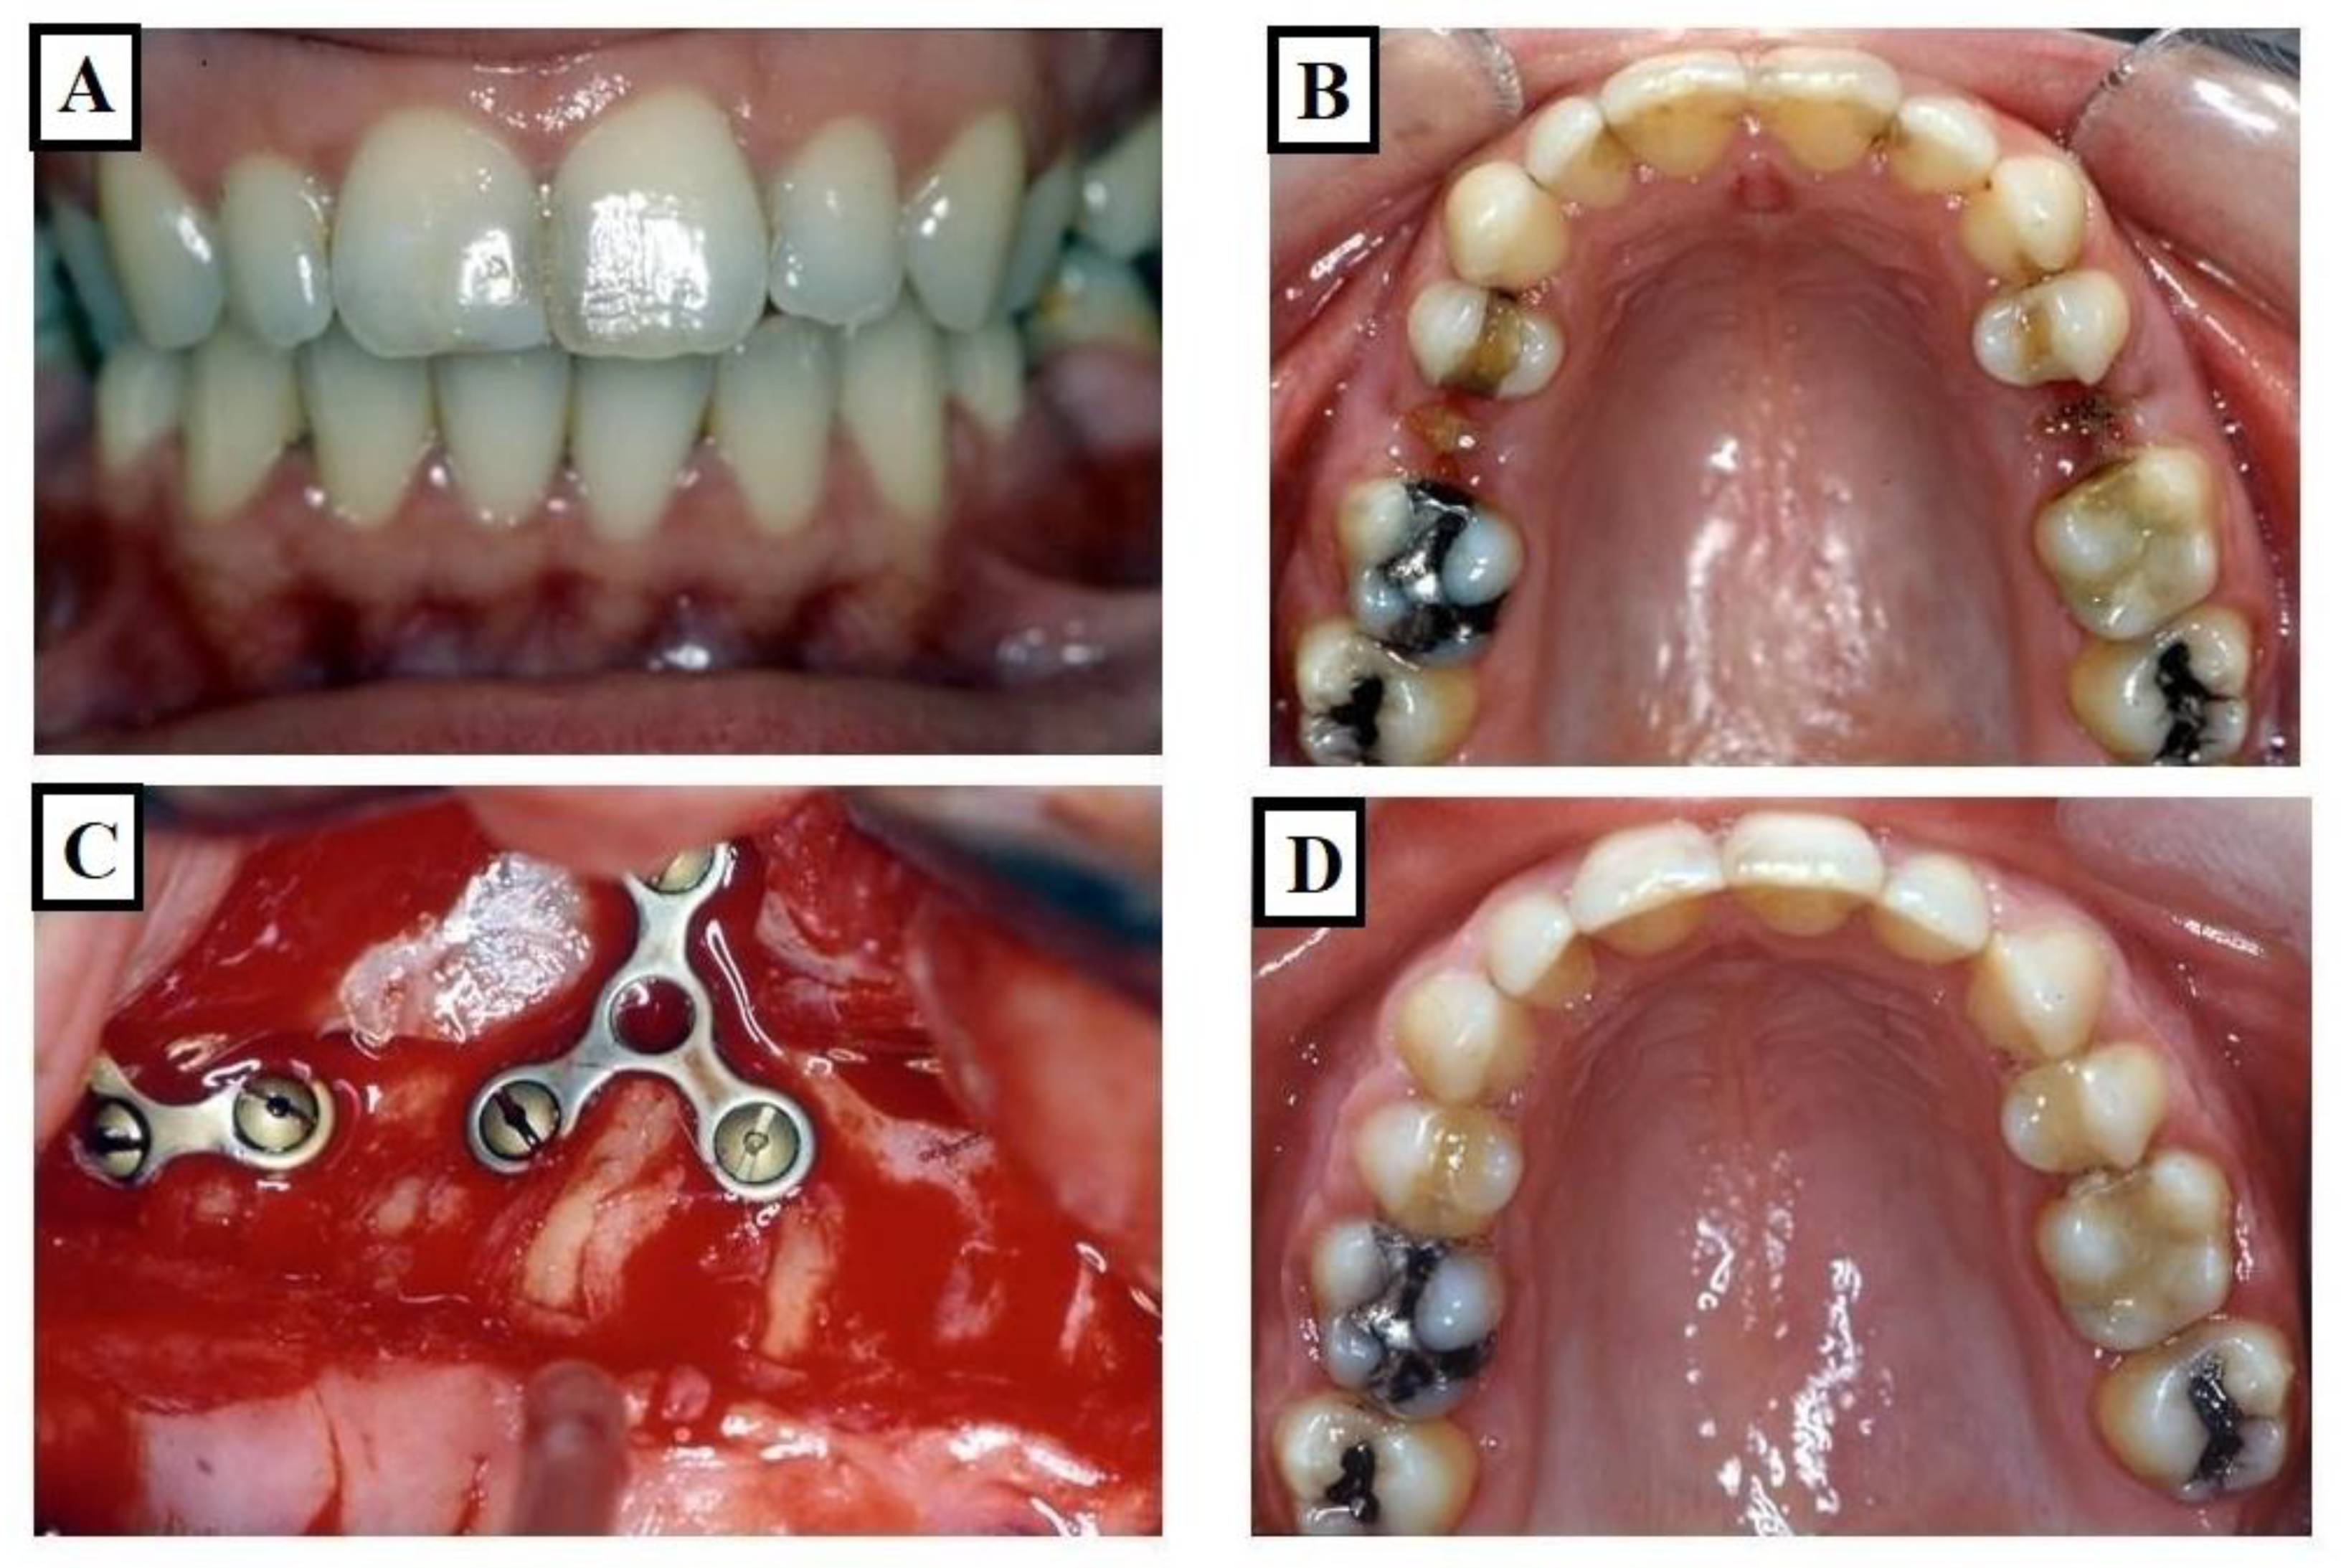

2.3. Dental Expansion

Research by Harrell [21] Davies [22] and Saravanan [23] has underscored that individuals at risk of periodontal disease exhibit a better long-term prognosis when working and nonworking interferences are eliminated. In the context of transverse deficiencies, the reduction in buccal alveolar bone associated with skeletal expansion may lead to weakened gingival tissues and an increased risk of gingival recession (Figure 4A–D). Thus, normalizing the transverse jaw connection not only eliminates an exaggerated Wilson curve and nonworking interferences but may also be advantageous for adult individuals susceptible to periodontal concerns, potentially preventing such risks in younger patients. By elucidating the relationship between transverse deficiencies, dental expansion, and the subsequent risk of gingival recession, this study emphasizes the importance of considering periodontal implications in orthodontic treatment planning.

Figure 4.

Images of a patient who underwent dental expansion of the upper jaw and an upper jaw osteotomy. (A,B) show the case before the treatment, while (C,D) show during the operation on the upper jaw; fissures in the bone were observed. This is associated with dental and alveolar expansion.